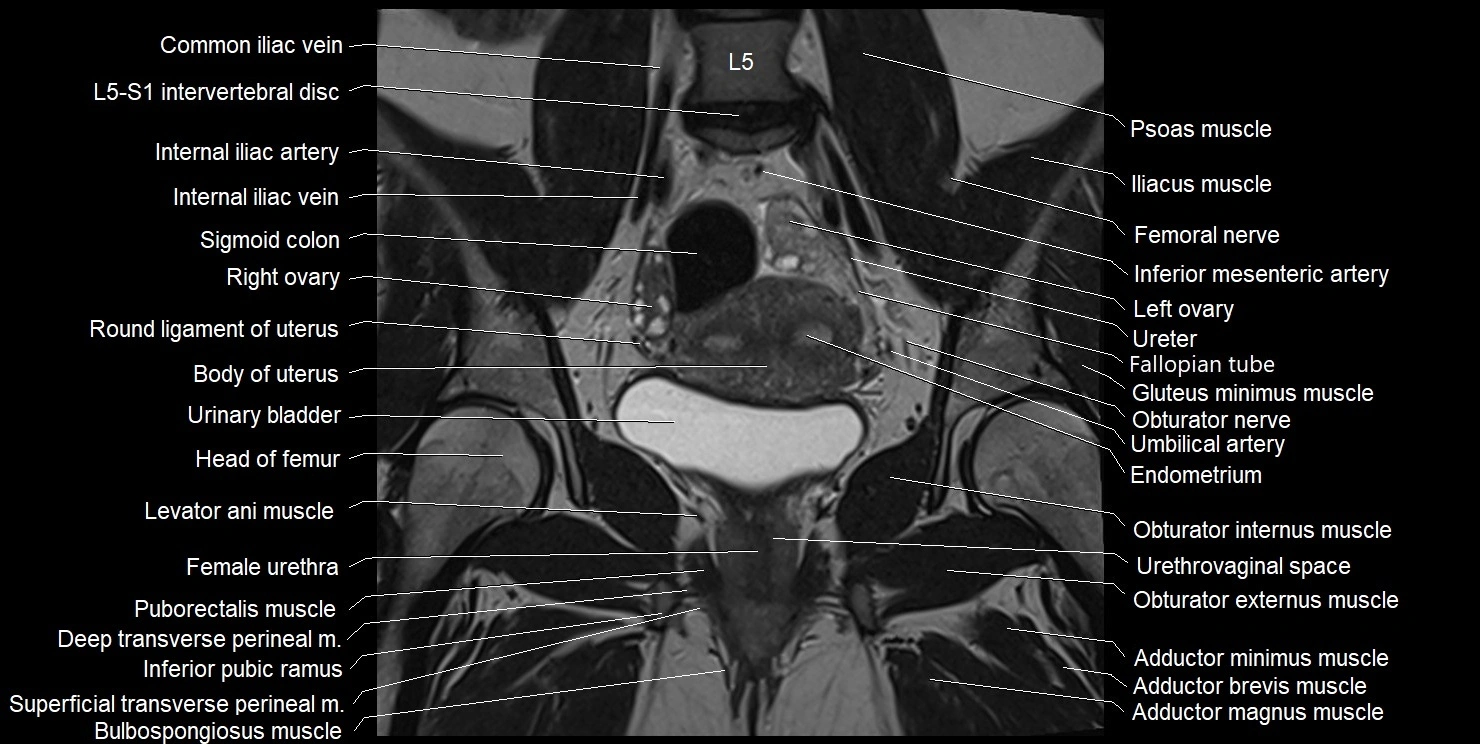

- Adductor brevis muscle

- Adductor longus muscle

- Adductor magnus muscle

- Adductor minimus muscle

- Bulbospongiosus muscle (Female)

- Common iliac vein

- Deep transverse perineal muscle

- Endometrium of uterus

- Fallopian tube

- Female urethra

- Femoral nerve

- Gluteus minimus muscle

- Head of femur

- Iliococcygeus muscle

- Inferior mesenteric artery (IMA)

- Internal iliac artery

- Internal iliac vein

- Left ovary

- Levator ani muscle

- Obturator externus muscle

- Obturator internus muscle

- Obturator nerve

- Puborectalis muscle

- Right ovary

- Round ligament of uterus

- Superficial transverse perineal muscle

- Umbilical artery

- Urethrovaginal space

- Urinary bladder

- Uterine venous plexus